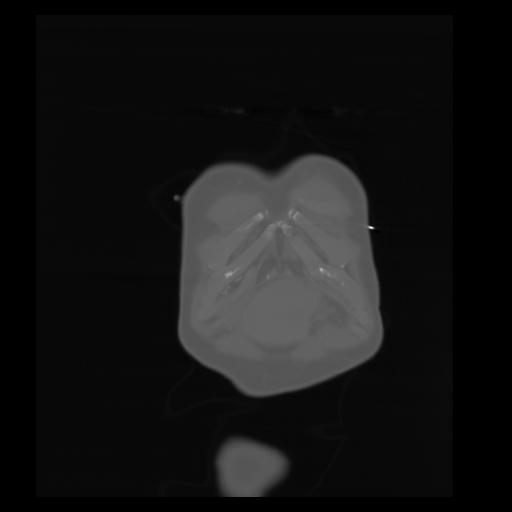

29 CUERPO,CE,Coronal,3.000,CUERPO,Coronal,